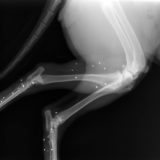

Les tiques

Ces acariens de la famille des arachnides (comme les araignées) sont eux aussi présents toute l’année, sauf au plus fort de l’hiver lorsque les températures sont négatives. Le printemps est l’une de leurs saisons préférées, puisqu’elles chassent en particulier dans les herbes hautes et qu’elles adorent les températures de 15 à 20°C ! Elles posent non seulement problème du fait de la gêne qu’elles occasionnent lorsqu’elles se nourrissent sur l’animal porteur, mais aussi et surtout parce qu’elles peuvent transmettre des maladies graves aux chiens et aux chats, comme la piroplasmose, l’ehrlichiose, ou la maladie de Lyme (borréliose).